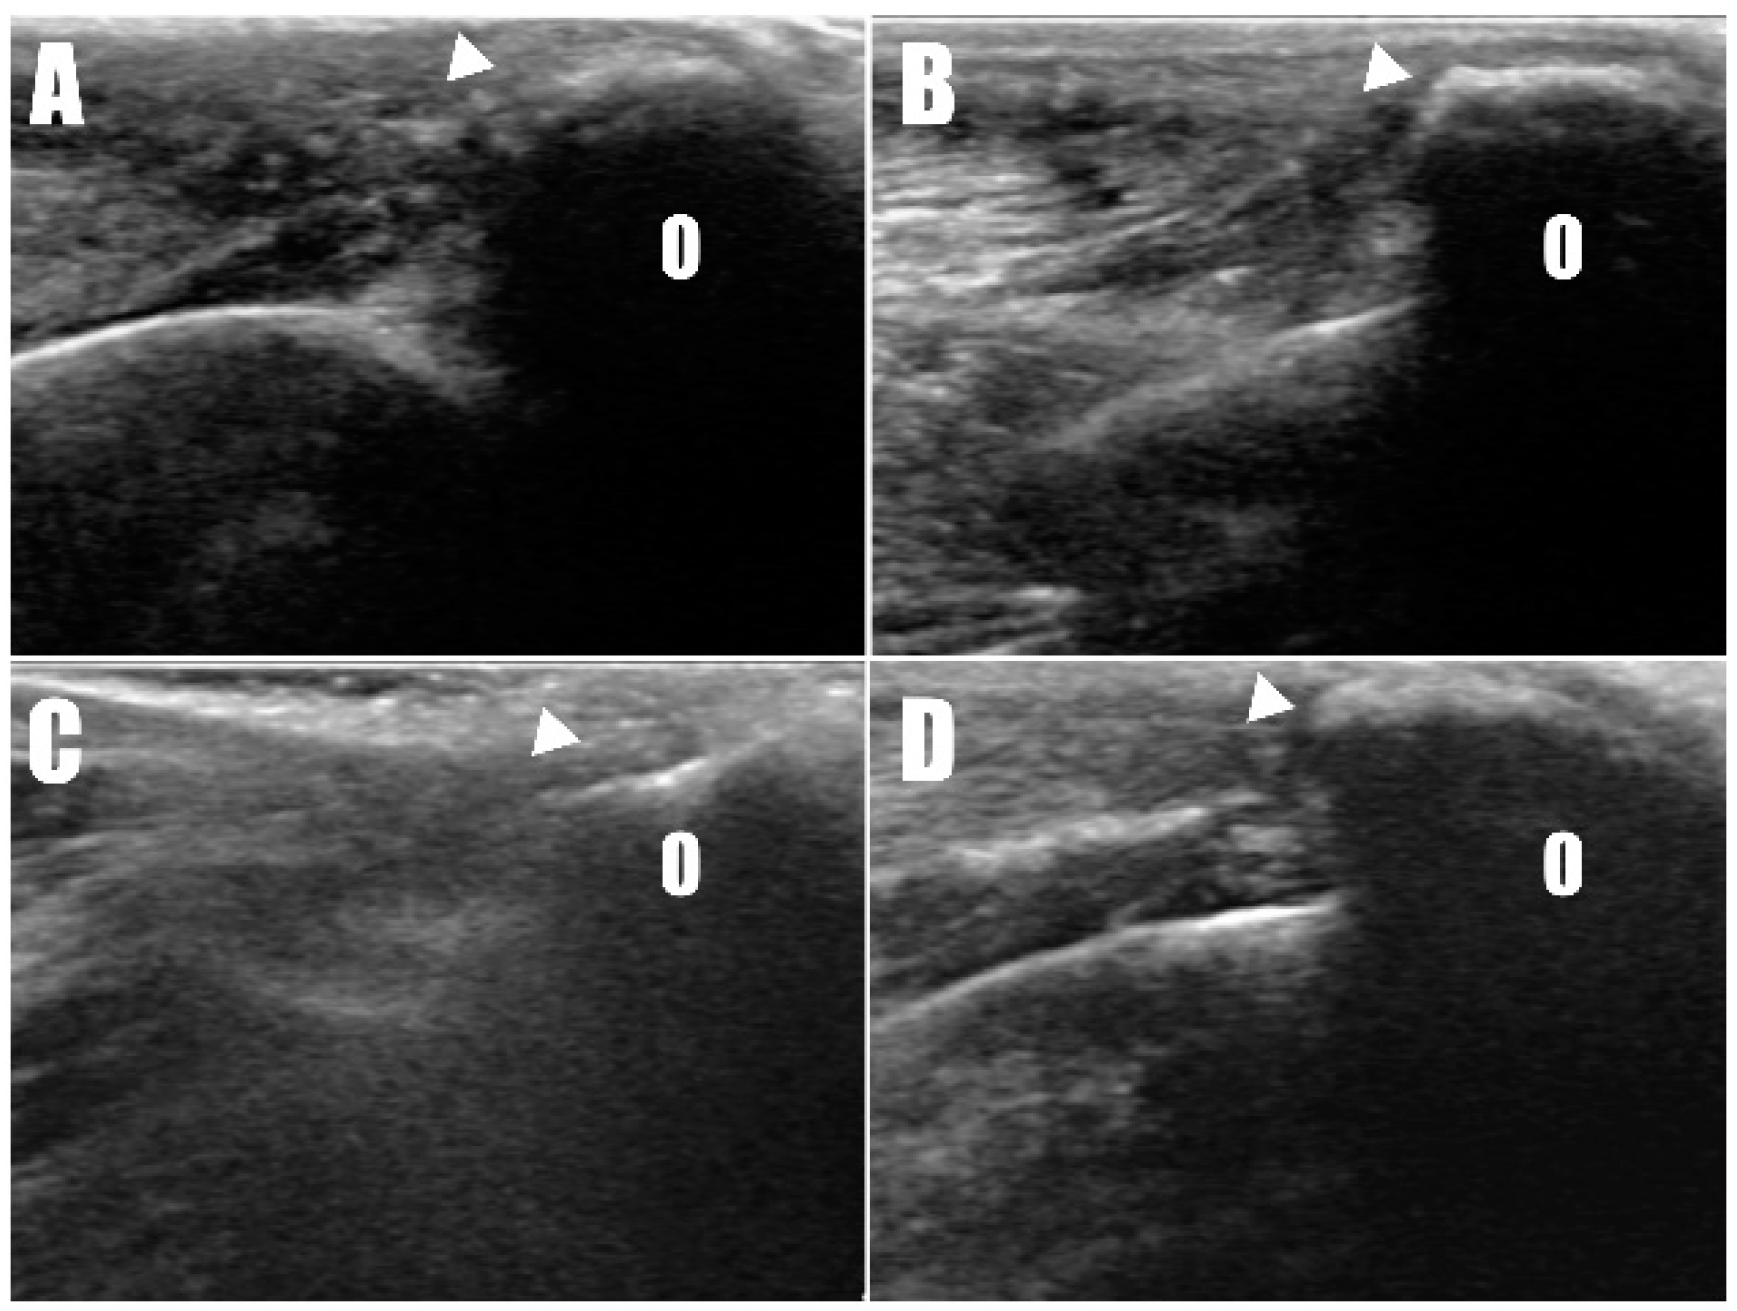

Figure 2A,B), and ultrasonography identified defects (

Figure 3A,B) at the triceps brachii tendon and olecranon junction, accompanied by inflammation and edema. Notably, the distal end of the proximal tendon appeared hyperechoic compared with the normal tendon. Based on the diagnosis of bilateral triceps brachii tendon disruption, believed to be of traumatic origin, and with the exact cause remaining open to interpretation, surgical repair was indicated. The initial management of the open wounds involved sugar dressing and debridement. Pre-anesthetic evaluation through blood samples, assessing electrolytes, and complete blood count (CBC), revealed all values within normal limits.

Postoperative radiographs and ultrasound images (

Figure 6) were taken to confirm the position and connectivity (

Radiography (

Figure 6C,D) and ultrasonography (

Figure 7C,D) six months postoperatively confirmed that the transverse hole of the right side healed without any complications, and the bilateral triceps brachii tendons were well-maintained and attached to the olecranon, with no specific changes in internal echogenicity or echotexture. MRI (